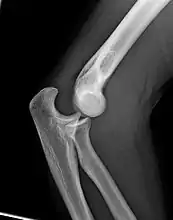

Carrying angle

Normal radiograph; right picture of the straightened arm shows the carrying angle of the elbow

When the arm is extended, with the palm facing forward or up, the bones of the upper arm (humerus) and forearm (radius and ulna) are not perfectly aligned. The deviation from a straight line occurs in the direction of the thumb, and is referred to as the "carrying angle".[22]

The carrying angle permits the arm to be swung without contacting the hips. Women on average have smaller shoulders and wider hips than men, which tends to produce a larger carrying angle (i.e., larger deviation from a straight line than that in men). There is, however, extensive overlap in the carrying angle between individual men and women, and a sex-bias has not been consistently observed in scientific studies.[23]

The angle is greater in the dominant limb than the non-dominant limb of both sexes,[24] suggesting that natural forces acting on the elbow modify the carrying angle. Developmental,[25] aging and possibly racial influences add further to the variability of this parameter.